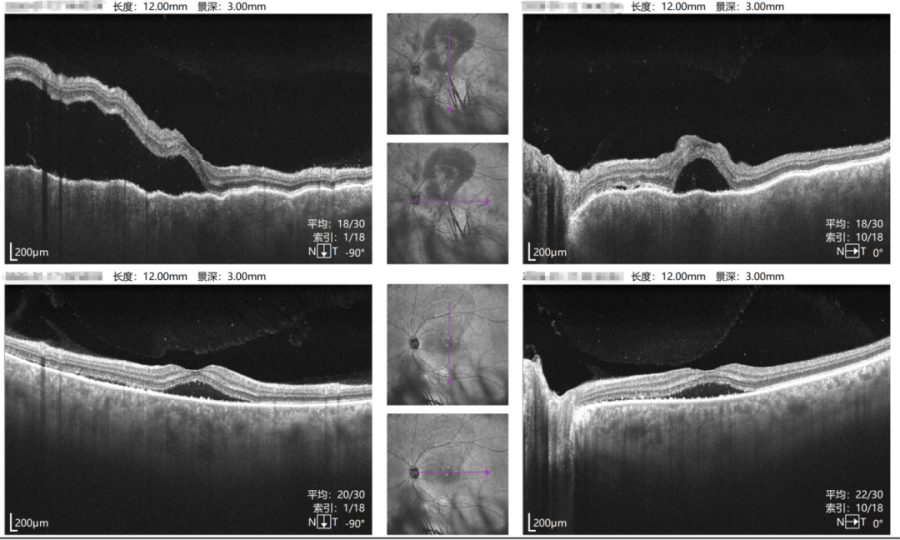

左眼治疗前后对比